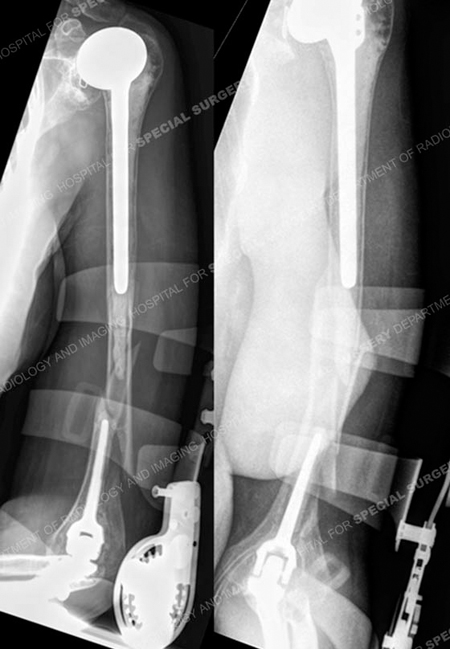

Anteroposterior and lateral fluoroscopic images (left images) demonstrating adequate fixation and alignment following open reduction and internal fixation and radiographs at 7 months postoperatively (right images) demonstrate a healed periprosthetic humerus fracture.

A 48-year-old female was referred to Dr. David L. Helfet, 2 days following a fall from a standing height onto her left upper extremity. Radiographs revealed a periprosthetic fracture above a cemented total elbow replacement and below a cemented humeral component of a total shoulder replacement. Her history was also significant for osteoporosis. Open reduction and internal fixation (ORIF) was performed with placement of a 3.5mm extra-articular distal humeral locking plate posterior-laterally and a 3.5mm reconstruction plate along the medial column in a 90-90 construct with multiple interfragmentary lag screws. She returned for routine follow-up and at 7 months radiographs illustrate a healed periprosthetic humerus fracture and she has returned to activities of daily living with resolution of pain.

Anteroposterior, oblique and lateral radiographs revealing a periprosthetic humerus fracture between a cemented long stemmed humeral component and a cemented standard length elbow component.